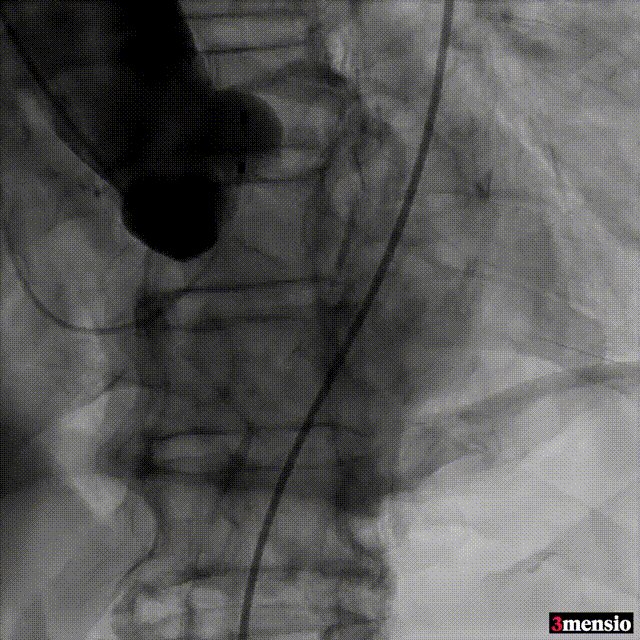

跨瓣

20mm球囊预扩

标准位释放定位